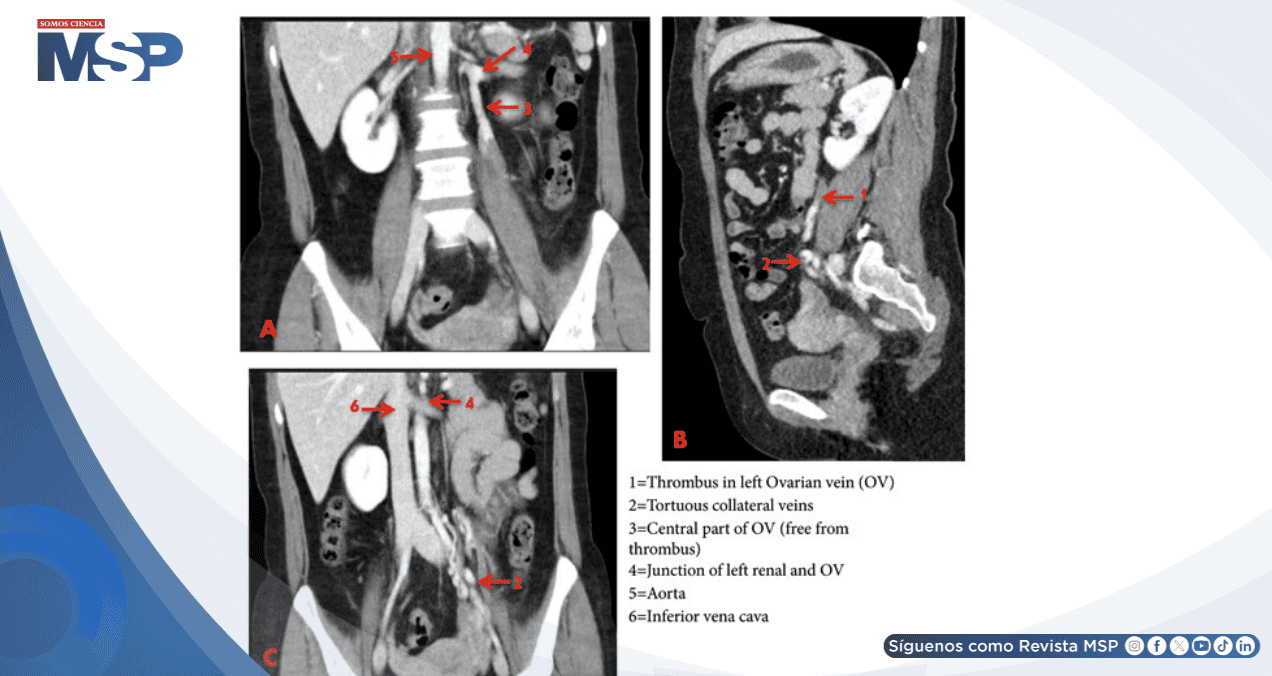

Ante la falta de hallazgos concluyentes en la ecografía y radiografía simple de abdomen, se realizó tomografía computarizada abdominal con contraste intravenoso. Las imágenes revelaron trombosis de la vena ovárica izquierda con venas anexiales dilatadas y tortuosas. El trombo se extendía centralmente, aunque la confluencia con la vena renal izquierda permanecía completamente permeable.

La tomografía computarizada con contraste demostró ser la modalidad diagnóstica de elección, ofreciendo sensibilidad y especificidad cercanas al 100%. Los hallazgos típicos incluyen defectos de llenado en la vena ovárica con dilatación o tortuosidad de las venas colaterales, precisamente lo observado en este caso.